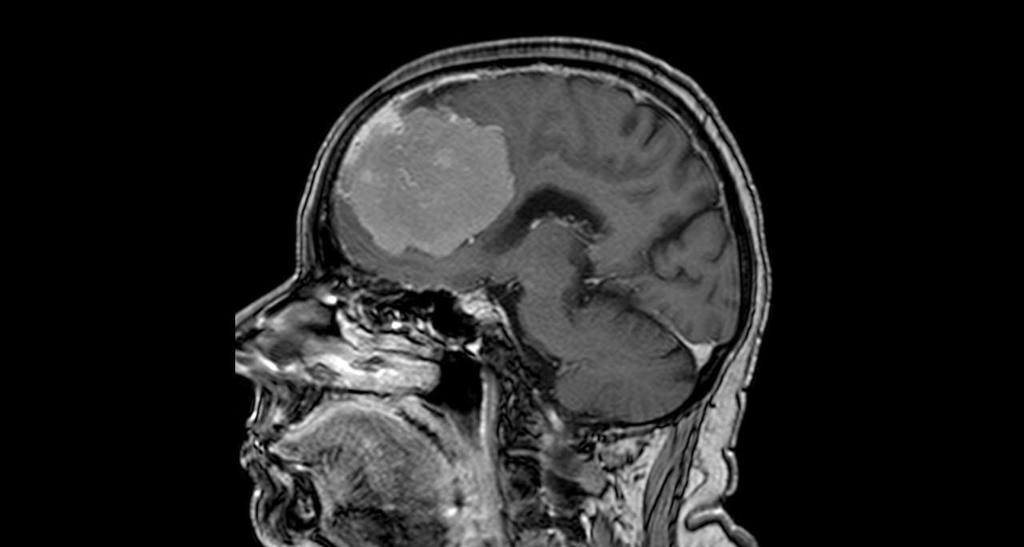

80-летняя женщина поступила в Воронежскую больницу скорой медицинской помощи №1 с подозрением на инсульт — у неё были проблемы с речью и слабость в правой руке. При стандартном обследовании с помощью компьютерной томографии выяснилось, что инсульта нет.

Однако была обнаружена опухоль в обеих лобных долях мозга размером 6х7х8 см.

Подобные новообразования так или иначе затрагивают важные участки мозга – кровеносные сосуды и зоны, отвечающие за речь и движение. Дополнительное исследование с контрастом показало, что опухоль окутывала магистральные сосуды Велизиевого круга – переднюю мозговую артерию, а также прорастала в переднюю треть сагиттального синуса (один из наиболее крупных венозных коллекторов головного мозга) и закрывала его.